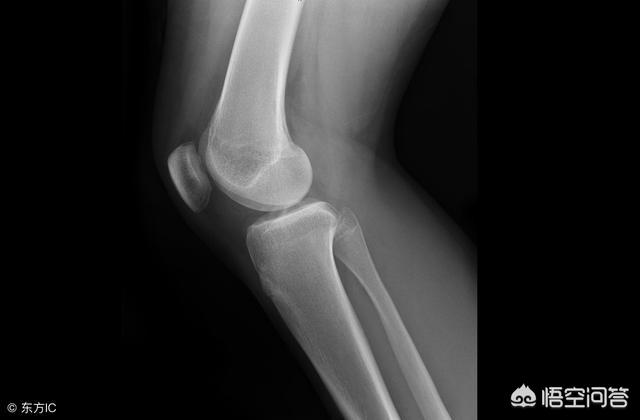

胸部X線検査:肺感染、肺腔、気管の問題、食道の問題、心陰影の大きさ、水胸の有無などを調べる。特に家族に油症や喫煙歴がある場合は、胸部X線検査が必要です。

レントゲンは撮影回数で課金され、通常、正面と側面の1部位で約100ドル。X線はCTやMRよりも比較的安価である。

変形性膝関節症の診断には、通常のX線検査で十分であり、CTやMRIなどの検査は通常必要ない。

したがって、患者が変形性関節症に罹患しているかどうかを診断するには、経験豊富な整形外科医による手技検査とともに、通常のX線検査を行えば、通常は十分である!

変形性膝関節症の患者では、膝関節腔の狭小化、軟骨下骨硬化および/または嚢胞変性、関節縁の骨障害形成などがX線写真で見られる主な症状である。

患者に外傷歴がある場合、あるいは関節靭帯の断裂や半月板損傷などが疑われる場合、医師は患者に磁気共鳴画像法(MRI)を受けるよう勧める。MRIは腫瘍などの除外にも使用できる。また、通常のX線検査よりもはるかに高額で、スキャニングMRIは850ドル++、エンハンストMRIは1400ドル++、X線検査は120ドル++程度である。